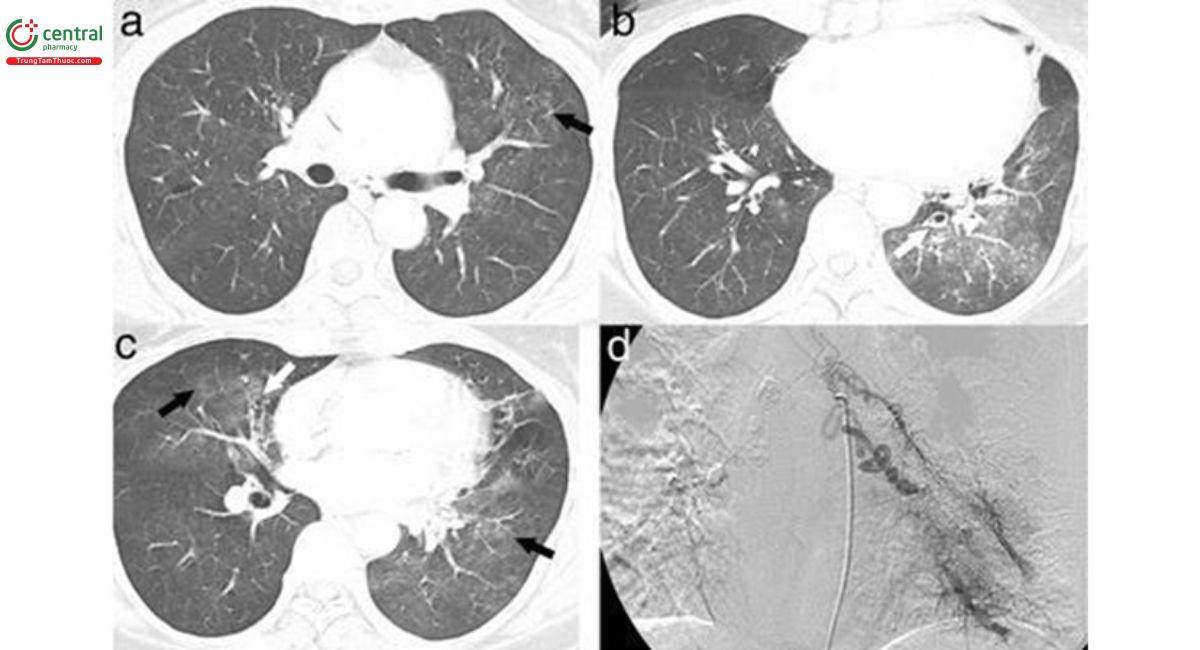

5.2 Đánh giá vị trí xuất huyết nhu mô phổi và đường dẫn khí

CLVT có thể xác định chính xác vị trí chảy máu trên 63-100% trường hợp ho ra máu. Hậu quả chảy máu lấp đầy các phế nang và đường dẫn khí gây ra hình ảnh “đông đặc” hoặc “tổn thương dạng kính mờ”. Cục máu đông cũng có thể hình thành làm bít tắc nhánh phế quản gây xẹp phổi [8]. Những dấu hiệu trên không đặc hiệu, gặp trong nhiều nguyên nhân khác nhau, nhưng có thể giúp dự đoán vị trí chảy máu. Trường hợp có nhiều vị trí có tổn thương dạng kính mờ, vị trí chảy máu được xác định là ở phần thùy phổi có kích thước lớn và đậm độ cao nhất [9].

![Hình 1. Các tổn thương kính mờ trên bệnh nhân ho ra máu (các mũi tên). Phần tổn thương kính mờ tại thùy dưới phổi (T) là ưu thế nhất, xác định vị trí xuất huyết [9].](/images/item/ho-ra-mau-1.jpg)

5.3 Đánh giá nguyên nhân ho ra máu

Các nguyên nhân HRM có thể phát hiện trên CCLVT như giãn phế quản, ung thư phổi, nhiễm trùng phổi cấp hoặc mạn (đặc biệt là lao và nấm phổi) và phù phổi do tim. Một lợi điểm nữa của CLVT đa dãy đầu dò là khả năng hiển thị những đường dẫn khí xa vượt quá khả năng của nội soi phế quản. Hình ảnh “quả cầu nấm” với dấu hiệu liềm khí rất đặc hiệu cho nguyên nhân ho ra máu do nấm phổi, đồng thời cũng chỉ điểm vị trí xuất huyết. Cần lưu ý, đối với những trường hợp viêm phổi hoại tử gây HRM, cần thiết chụp CLVT mạch máu để phát hiện các phình mạch [8].